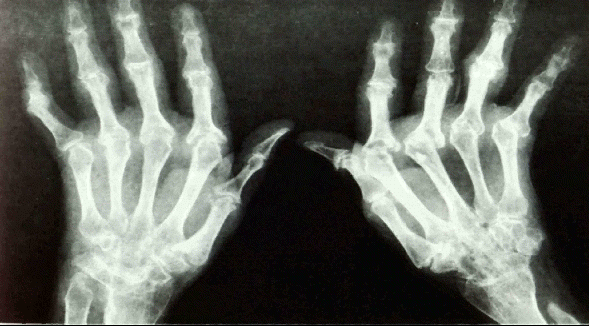

류마티스 관절염 환자의 손 X-선 사진

양손의 관절이 모두 심하게 파괴되어 있고 손가럭의 모양이 변형되어 있다.